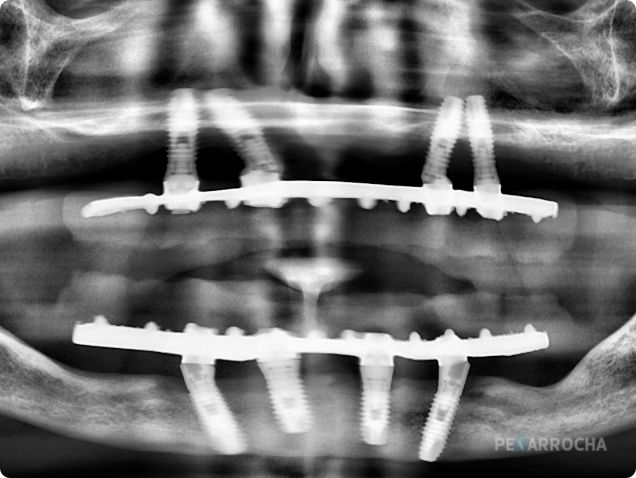

radiografia caso real implantes all on four en valencia dres penarrocha cirugia e implantologia oral en valencia